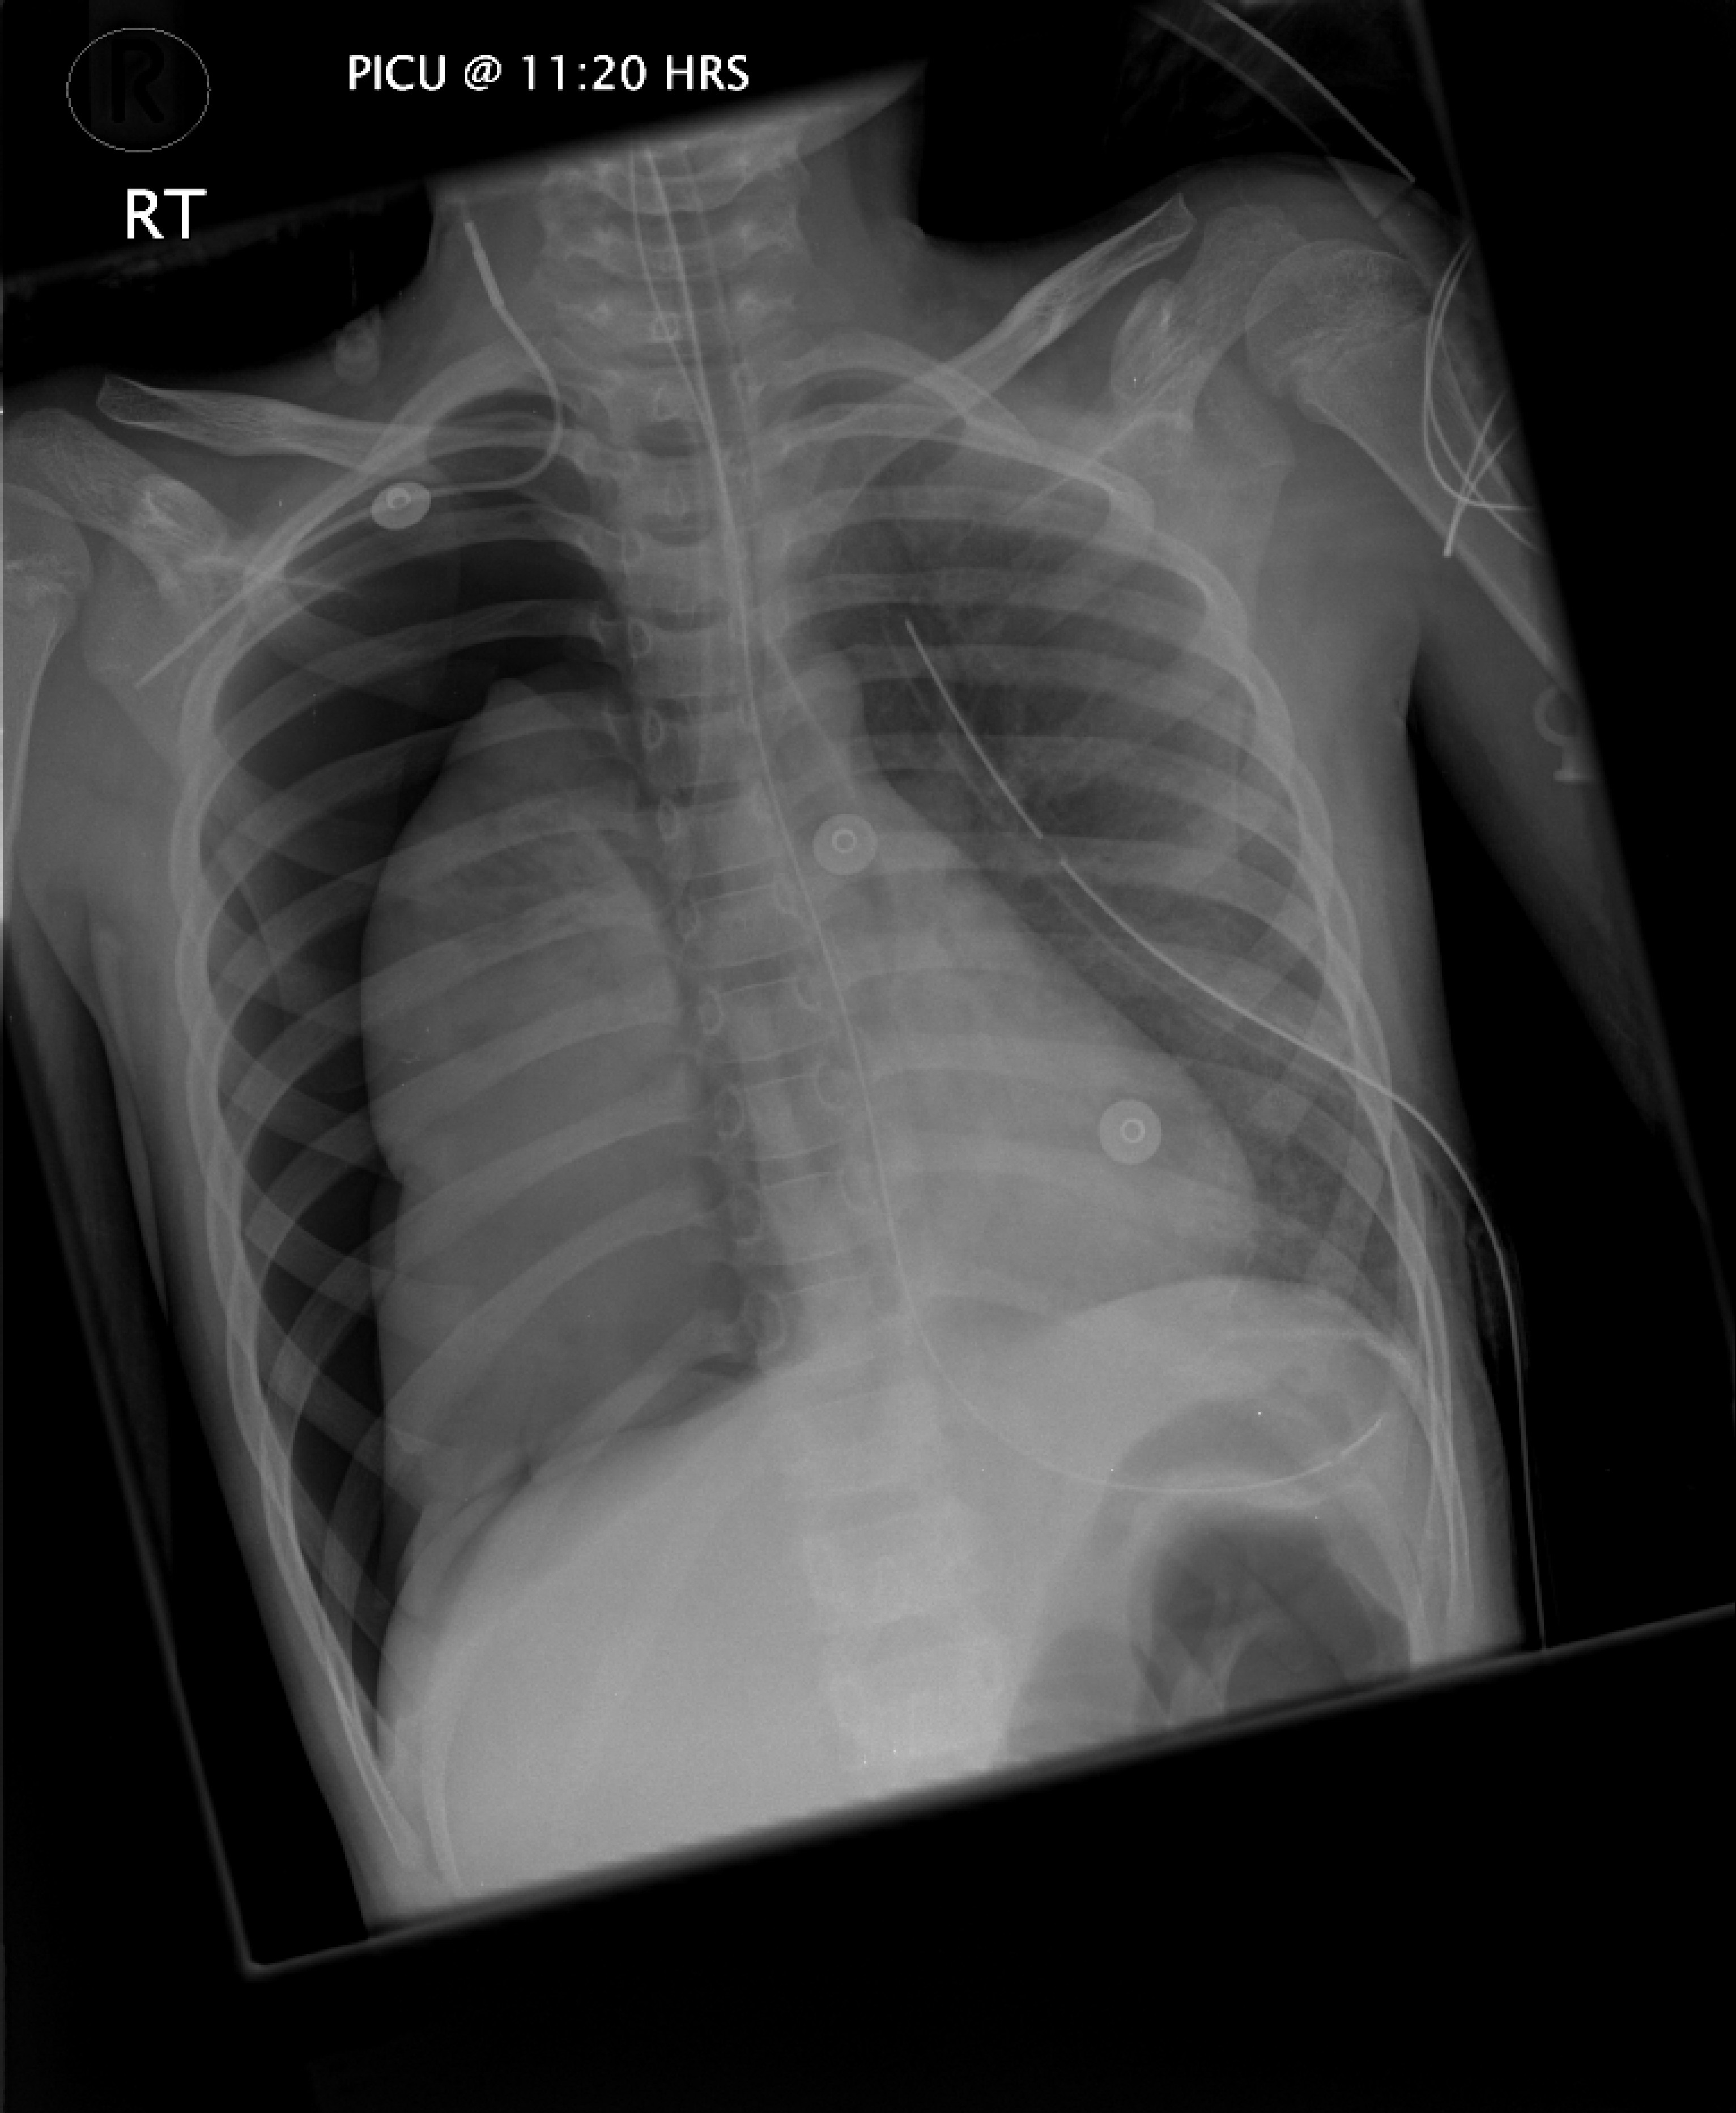

He could have problems related to his ventilation or specific to his condition. The ET tube might have become obstructed with blood or become displaced or he could have septicaemia. He might have had profound intrapulmonary hemorrhage. The following CXR shows he had a pneumothorax. There is an obvious concern regarding the prognosis in this child heightened by the acute deterioration. With continued bleeding there is an increasing concern of fatal pulmonary hemorrhage associated with the risk of deterioration unrelated to the diagnosis of pulmonary capillaritis. It seems appropriate to consider the role of more invasive life supportive modalities.